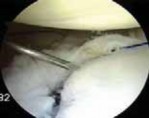

Following the diagnostic sweep, two anterior working portals are established using an outside-in spinal needle localization technique. The anterosuperior portal is typically placed just anterior to the acromioclavicular joint, entering the joint through the rotator interval superior to the biceps tendon; this serves primarily for fluid management and suture retrieval. The critical anteroinferior working portal is placed just superior to the upper border of the subscapularis tendon, ensuring an optimal trajectory (approximately 45 degrees to the glenoid face) for anchor insertion along the anteroinferior glenoid rim. A clear cannula (typically 5.5 mm or 8.25 mm) is introduced to facilitate smooth instrument passage and suture management.

The foundation of a successful arthroscopic stabilization is the meticulous mobilization of the capsulolabral complex. In chronic cases, the torn labrum and IGHL frequently heal in a medially displaced position along the anterior glenoid neck (the ALPSA lesion). Using a combination of arthroscopic elevators, rasps, and electrocautery, the surgeon must aggressively liberate this tissue from the scapular neck. The release must extend inferiorly to the 6 o'clock position to adequately mobilize the inferior capsule. Once the tissue is freed and can be easily reduced to the articular margin, the anterior glenoid neck is lightly decorticated using a motorized burr or rasp. This critical step removes fibrous tissue and exposes bleeding cancellous bone, creating an optimal biological environment for robust soft-tissue healing.